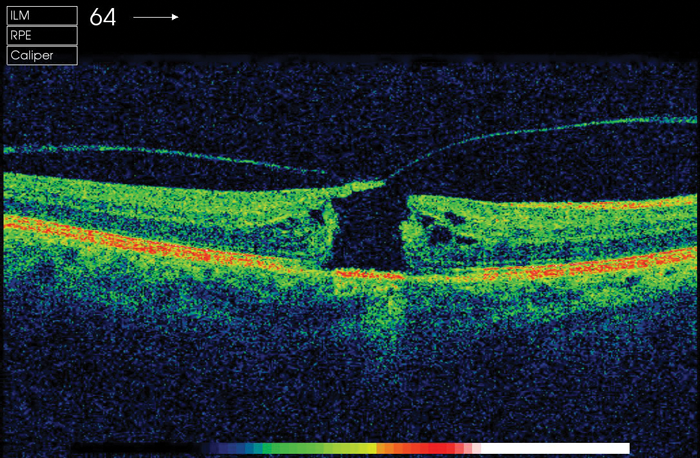

Macular holes: A brief review

The classification of macular holes has been modernised by OCT findings. This is a brief review and encompasses the historical literature on macular holes. A macular hole is an anatomical discontinuation of the neurosensory retina at the centre of the...